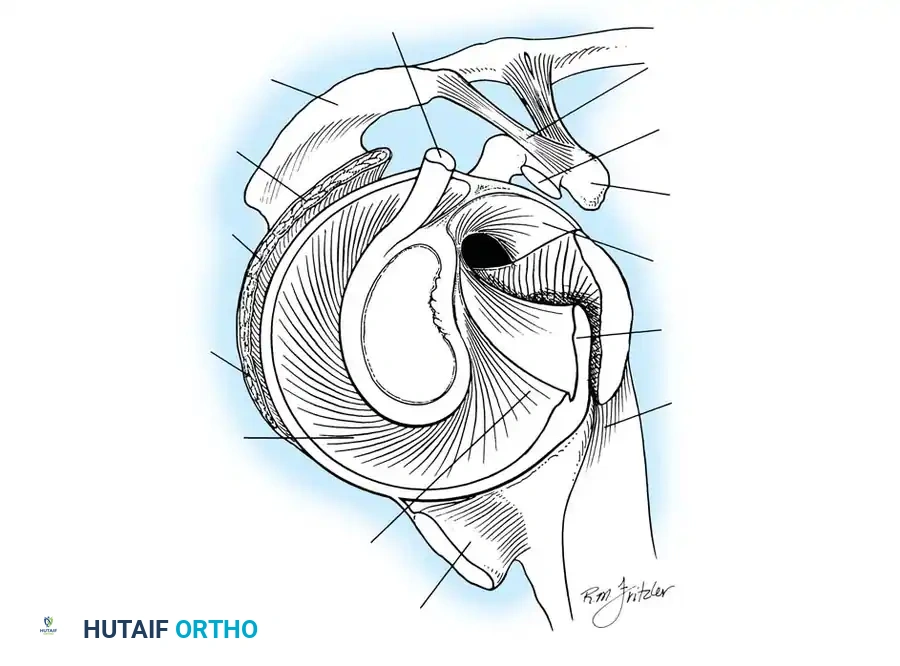

The Glenoid Labrum and Biceps Anchor

According to seminal studies by Howell et al., the effective depth of the glenoid is increased by 50% due to the presence of the fibrocartilaginous glenoid labrum. This structure acts as a bumper, increasing the humeral contact area to 75%. Integral to the superior glenoid labrum is the insertion of the long head of the biceps tendon, which blends indistinguishably into the posterior and anterior superior labrum. Matsen et al. conceptualized the labrum as a "chock block" that prevents excessive humeral head translation and rollback during physiological loading.

The shoulder joint capsule is inherently lax and thin, offering little resistance in isolation. However, it is reinforced anteriorly by three distinct capsular thickenings—the glenohumeral ligaments—which fuse intimately with the labral attachment on the glenoid rim. Turkel et al., alongside O’Brien, Warren, and Schwartz, have extensively mapped these structures.

- Superior Glenohumeral Ligament (SGHL): Attaches to the superior glenoid tubercle near the apex of the labrum, conjoined with the biceps anchor. It inserts onto the anterior aspect of the anatomical neck of the humerus. The SGHL is the primary restraint to inferior humeral subluxation at 0 degrees of abduction and serves as a primary stabilizer against anterior and posterior stress in the adducted arm. Harryman et al. demonstrated that tightening the rotator interval (which encompasses the SGHL and coracohumeral ligament) significantly decreases posterior and inferior translation.

- Middle Glenohumeral Ligament (MGHL): Features a wide origin extending from the SGHL along the anterior glenoid margin down to the junction of the middle and inferior thirds of the rim. It limits external rotation when the arm is in lower and middle ranges of abduction (45 degrees) but becomes redundant at 90 degrees of abduction.

- Inferior Glenohumeral Ligament (IGHL) Complex: The most critical static stabilizer. It attaches to the glenoid margin from the 2-o’clock to 3-o’clock positions anteriorly, extending to the 8-o’clock to 9-o’clock positions posteriorly. Its humeral attachment lies below the articular margin on the anatomical and surgical neck. O’Brien et al. described this complex as a "hammock-like" structure consisting of a thickened anterior band, a posterior band, and a thinner axillary pouch.

Glenoid Preparation and Labral Repair

The essential step in restoring stability is the anatomical reduction of the capsulolabral complex to a bleeding bone bed on the anterior glenoid rim.

- Debridement: The anterior glenoid neck is decorticated using a motorized burr, rasp, or osteotome to create a bleeding cancellous bed. This promotes robust biological healing of the repaired labrum.

- Mobilization: The scarred, medially displaced labrum (ALPSA lesion) must be fully mobilized using a periosteal elevator until the subscapularis muscle belly is visible anteriorly. The tissue must float freely to be shifted superiorly and laterally.

- Anchor Placement: Suture anchors (typically 3 to 4) are placed along the articular margin of the anteroinferior glenoid (from the 5:30 to 3:00 positions for a right shoulder). Anchors must be inserted at a 45-degree angle to the articular surface to maximize pullout strength and avoid joint penetration.